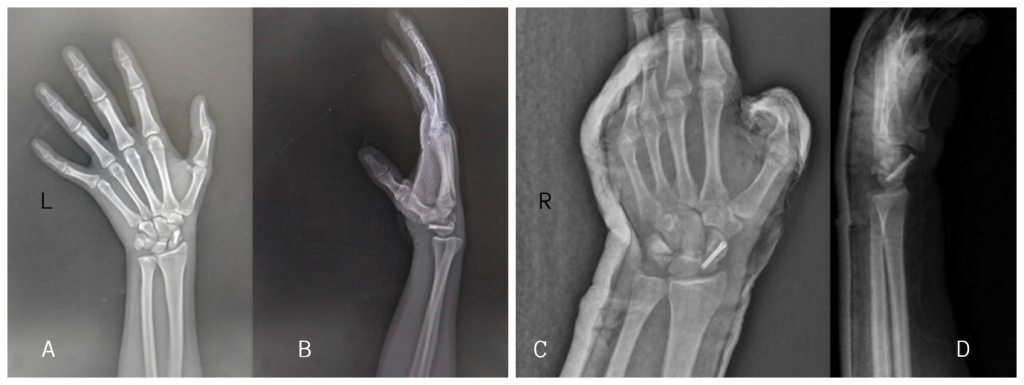

Patient was allowed with wrist mobilization after 4 weeks, and follow-up X-rays were done on subsequent visits to the outpatient department. Six-month follow-up X-rays show union in the bilateral scaphoid (Fig. 5). Clinically, the patient was able to carry out daily activities without pain. Grip strength was assessed using a dynamometer, and at 12-month follow-up, was found to be 90% of normal bilaterally. Functional assessment was performed using QuickDASH, Mayo Wrist score, and wrist ROM measured via goniometer. (Table 1) Our follow-up period was limited to 12 months. While this showed satisfactory union and functional outcomes, scaphoid-related complications such as avascular necrosis (AVN) and post-traumatic arthritis often manifest over longer durations. Continued monitoring is advised.

A 12-month follow-up, radiological evaluation using X-rays (Fig. 6), and CT confirmed complete union of the scaphoid fractures. Objective assessment revealed 100% trabecular bridging across the fracture sites in coronal, sagittal, and axial planes (Fig. 7), which is considered the gold standard indicator of union following internal fixation of scaphoid fractures [4]. According to the CT-based grading system, this finding corresponds to Grade 4, indicating complete osseous healing [5]. Furthermore, based on the scaphoid fracture healing score, the patient achieved the maximum score of 10, reflecting optimal bone consolidation and structural integrity [6]. These objective measures provided strong evidence of successful healing, allowing for full return to functional activities.

Figure 6: A 12-month follow-up X-ray of the bilateral wrist. Anteroposterior (a) view, and scaphoid (b) of the bilateral wrist.

Figure 7: A 12-month follow-up computed tomography showing complete bony union of left side axial and sagittal view (a and b), right side axial and sagittal view (c and d), and Coronal view (e).